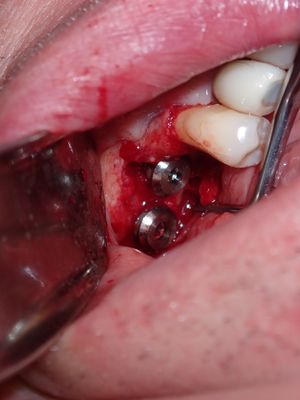

large amount of bone loss at time of exo 36/37 done 2 months ago. Good healing of bone except for small socket area at 36 region. buccal bone lower than palatal about 1mm, decided to place tissue level implants opposed to grafting, gaining back height is unlikely, difficult access case with large tongue. Implants placed with 36 about 1.5mm buccal exposed, 37, .5mm mesial exposed, healing abutments palced grafted all sites with sticky bone followed by collagen membrane soaked in prf fluid, 2 holes cut for implants. additonal fibrin membrance placed on buccal prior to suturing.